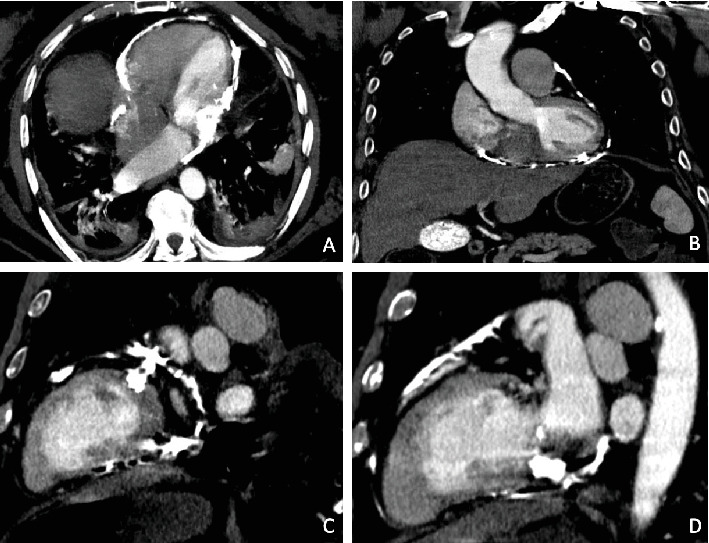

Despite advances in imaging and diagnostics, calcific constrictive pericarditis (CCP) remains a rare and challenging entity, often masquerading as other cardiopulmonary conditions, leading to delayed diagnosis. We present a 70-year-old male with a history of heart failure, atrial fibrillation (AF), cirrhosis, chronic obstructive pulmonary disease (COPD), and prior pleural effusion, who was admitted with acute hypoxic respiratory failure and AF with rapid ventricular response (RVR). Imaging revealed extensive pericardial calcifications, leading to a diagnosis of CCP. The patient's clinical course was marked by refractory hypotension, altered mental status, and progressive cardiohepatic syndrome. Given his high surgical risk, he was managed conservatively and transitioned to palliative care. This case underscores the diagnostic and therapeutic challenges of CCP, particularly in patients with complex comorbidities where surgical intervention is not feasible. It highlights the need for early recognition and individualized management strategies to optimize outcomes in this challenging subset of patients.

Abstract Image